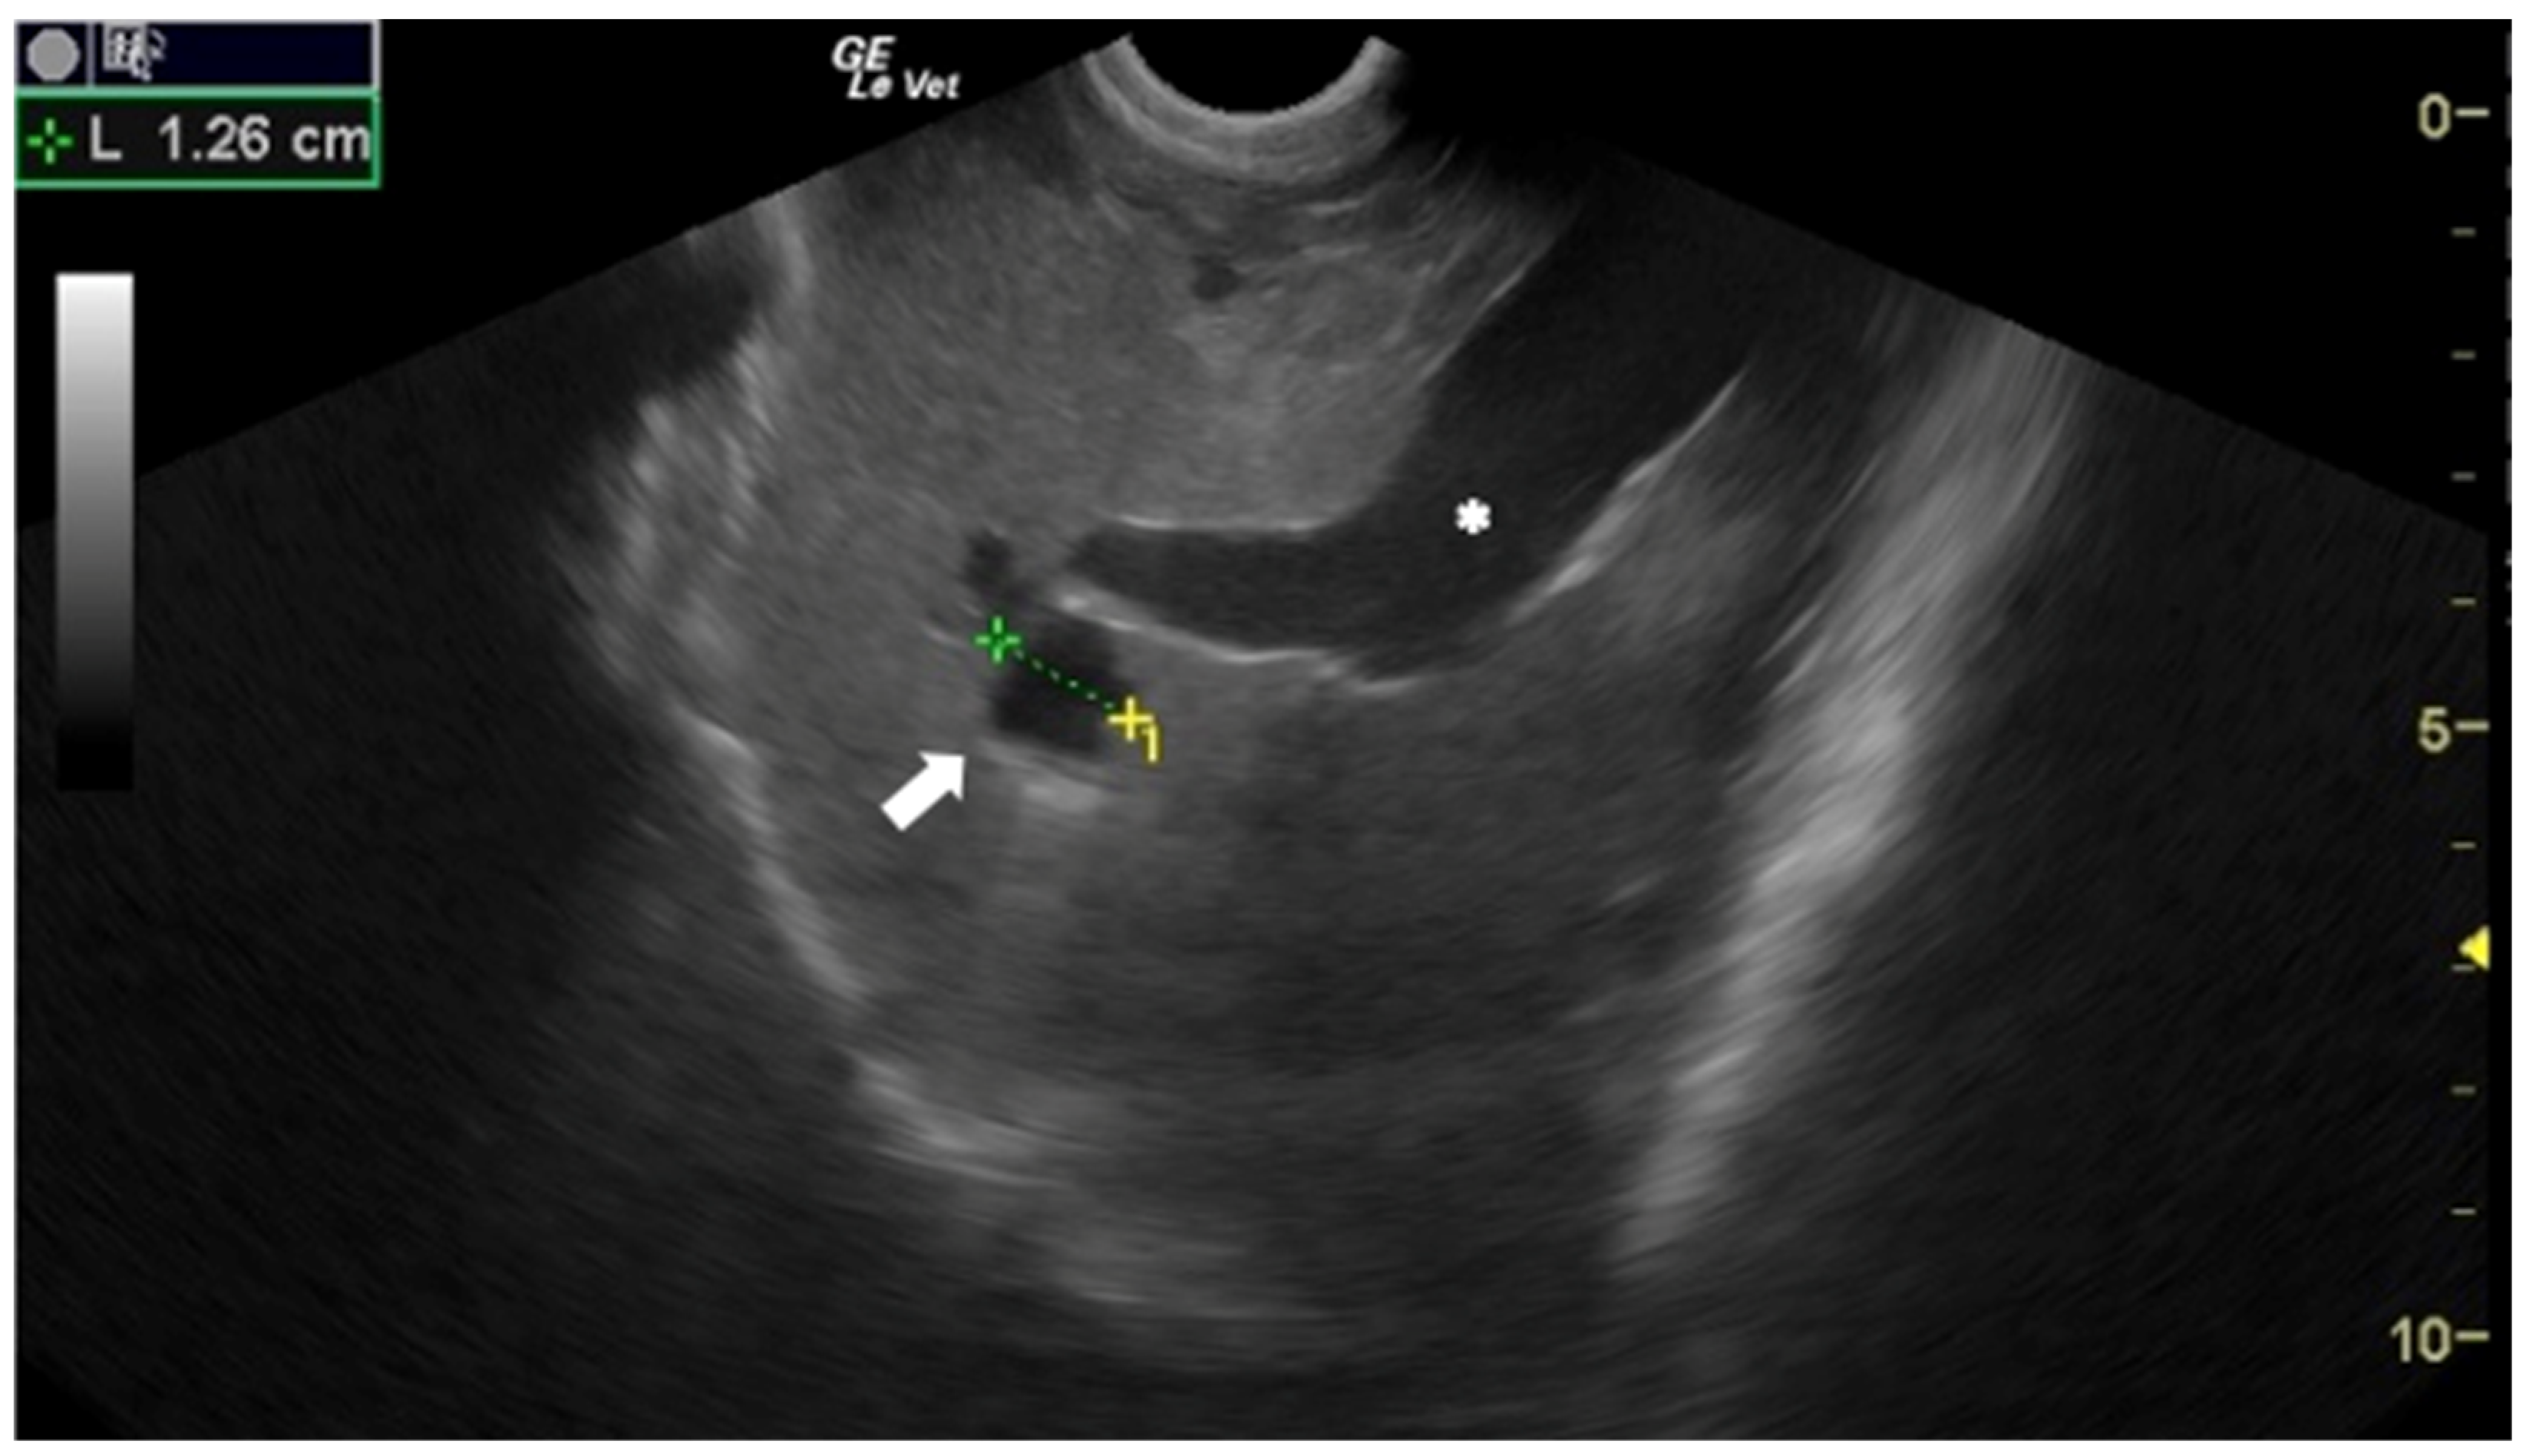

- Corda, A.; Dessì, G.; Varcasia, A.; Carta, S.; Tamponi, C.; Sedda, G.; Scala, M.; Marchi, B.; Salis, F.; Scala, A.; et al. Acute visceral cysticercosis caused by Taenia hydatigena in lambs: Ultrasonographic findings. Parasites Vectors 2020, 13, 568. [Google Scholar] [CrossRef]

- Corda, A.; Tamponi, C.; Meloni, R.; Varcasia, A.; Parpaglia, M.L.P.; Gomez-Ochoa, P.; Scala, A. Ultrasonography for early diagnosis of Toxocara canis infection in puppies. Parasitol. Res. 2019, 118, 873–880. [Google Scholar] [CrossRef]